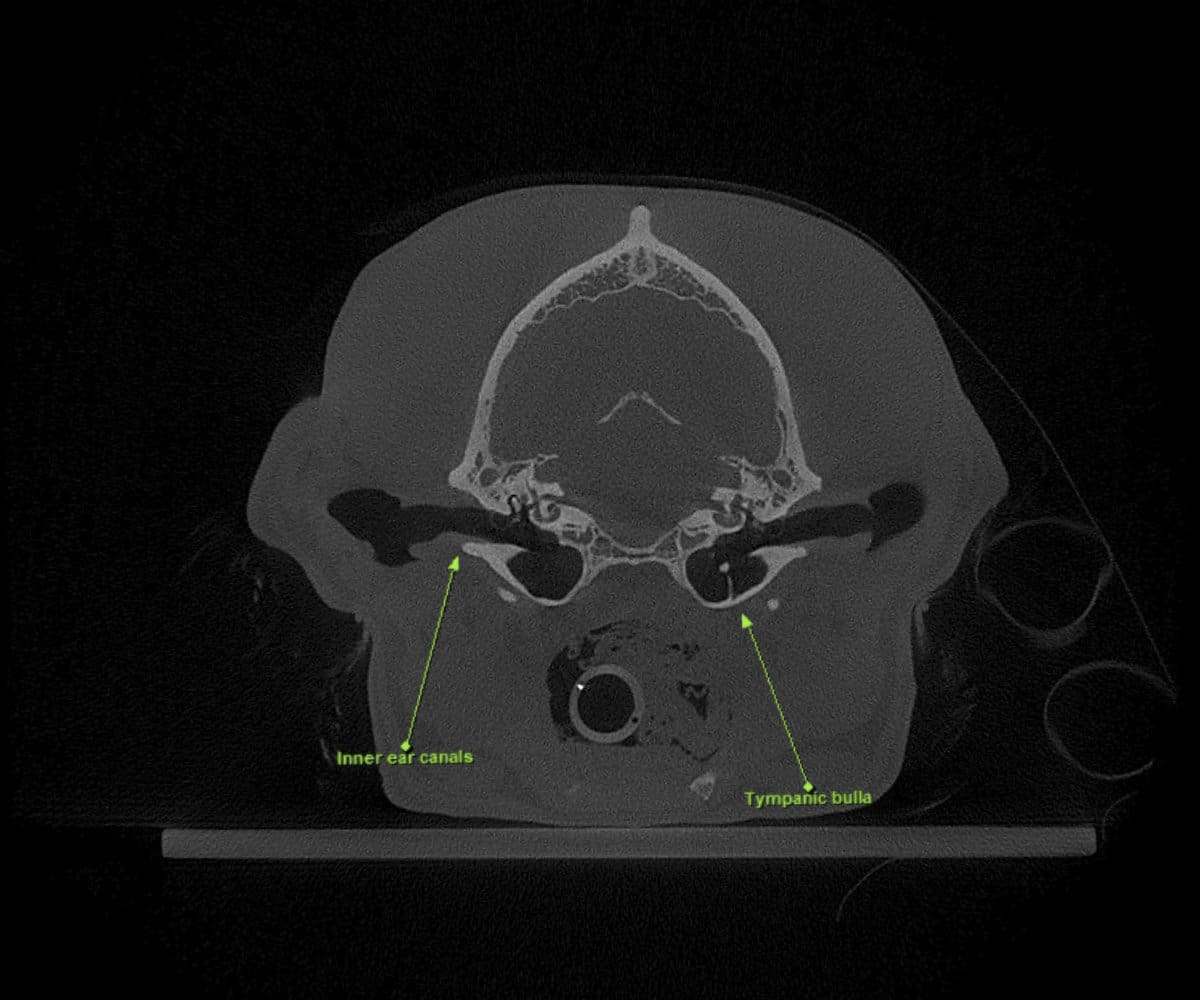

Animal Dental Care and Oral Surgery takes great pride in being at the forefront of veterinary care in Colorado, having introduced the pioneering cone beam computed tomography (CBCT) technology for our patients. While digital dental radiographs have been a cornerstone in veterinary dentistry diagnostics, providing invaluable insights into dental diseases in dogs and cats, they inherently present limitations as 2-dimensional images, often requiring considerable time during anesthesia.

In addressing these limitations, CBCT emerges as a pivotal advancement. Conducting a CBCT scan on our patients is characterized by minimal time and effort, effectively reducing anesthesia duration. Moreover, this technology facilitates the generation of a comprehensive 3D reconstruction of the teeth and skull, surpassing the constraints of traditional radiographs. This innovative approach empowers our veterinary professionals to identify oral pathologies that may have been missed on traditional radiographs.

Cone beam CT technology provides veterinarians with 3-dimensional images in far greater detail than dental radiographs. CBCT scans significantly decrease the amount of time a patient spends under anesthesia compared to the time it takes to complete dental radiographs.

Our CBCT VetCAT unit is easily rolled up to our treatment table and takes only 40 seconds to complete a scan. It has proven to be invaluable in the diagnosis and treatment planning for pets with periodontal, endodontic and cancerous disease conditions. It is also indispensable in the evaluating our trauma cases with jaw fractures.